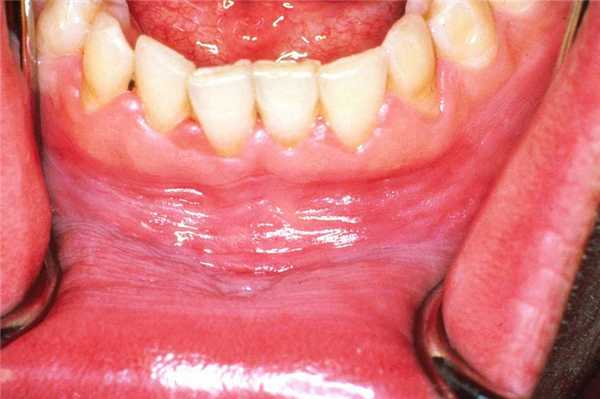

Данная форма лейкоплакии редко располагается на языке, но если такие случаи встречаются, то обычно поражению подвергается слизистая оболочка боковых поверхностей языка. Очаги изменения имеют округлую форму белого цвета. В месте расположения элементов сыпи сосочки языка сглажены. Элементы поражения, локализующиеся на слизистой дна полости рта, представлены белой, трудно снимающейся пленкой.

Эритроплакия. Пятно преимущественно красного цвета любой локализации. Как правило, поверхность неоднородная, могут отмечаться эрозии.